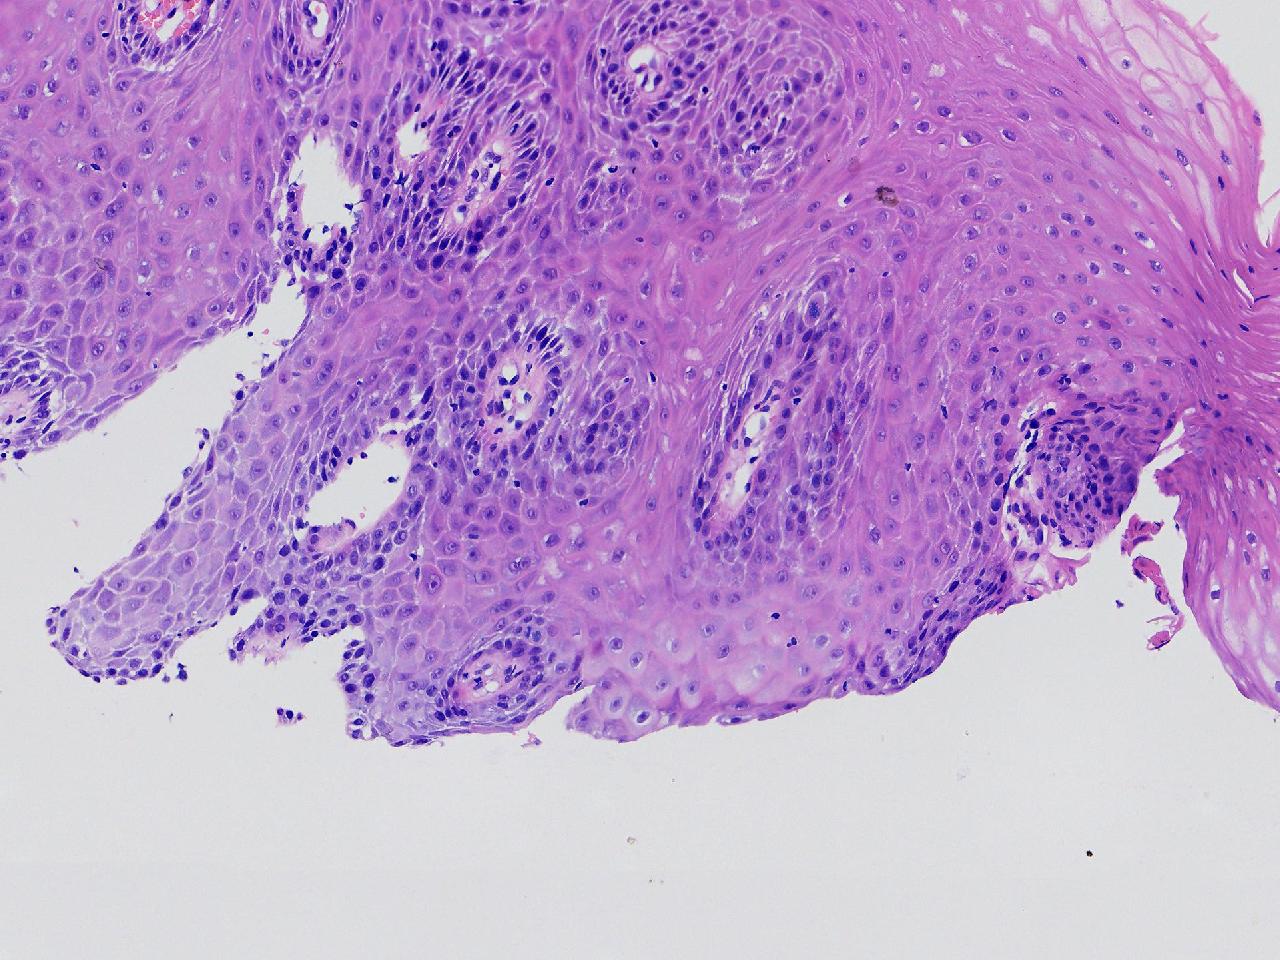

男,62岁,贲门口齿状线上见条状糜烂,活检1块,质软。

贲门口活检

灰白色不整形软组织1块,直径0.2厘米。

鳞皮乳头状增生伴慢性炎。